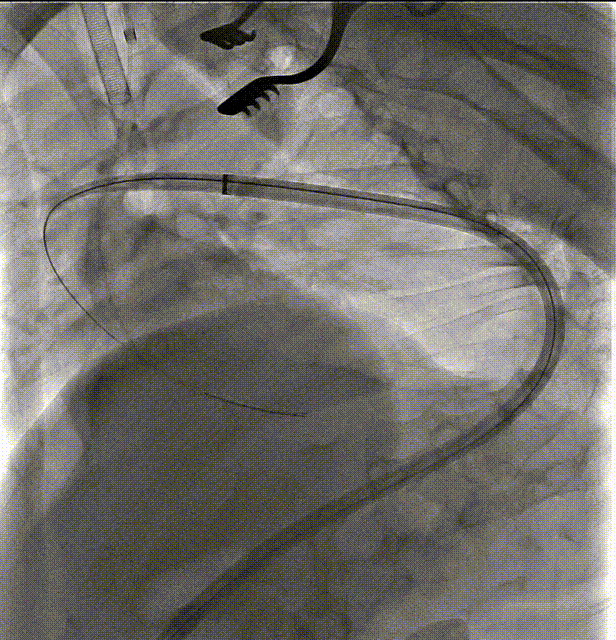

第一步、常规麻醉,消毒铺巾,分离显露左锁骨下动脉、左颈总动脉和左椎动脉备用。经右侧股动脉穿刺植入5F鞘,黄金标记猪尾导管升主动脉造影明确主动脉病变(图2)。

第二步、交换超硬导丝,置入Gore大鞘 DSF2065,顺利通过降主段以及主动脉缩窄处,近端到达无名动脉后缘。